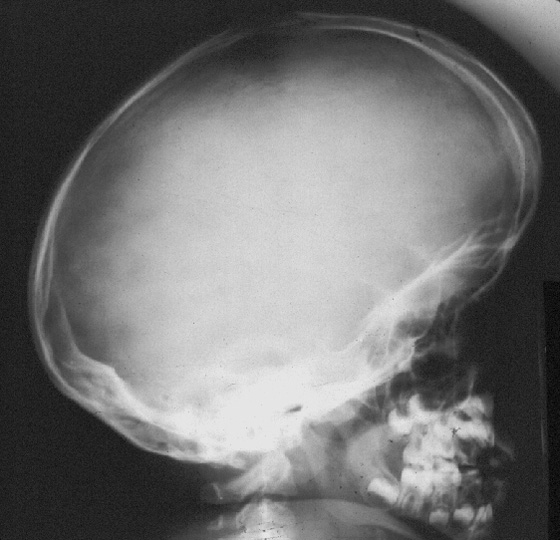

Ultrasound Frontal Bossing Achondroplasia : Diagnosis is based on radiological and clinical findings.

Ultrasound Frontal Bossing Achondroplasia : Frontal bossing, depressed nasal bridge.